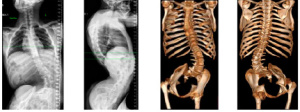

Сколиоз является одним из наиболее распространенных патологических состояний, по поводу которого проводят инструментальную фиксацию позвоночника. Независимо от этиологического фактора сколиотические деформации сопровождаются не только отклонением оси позвоночника, но и изменениями формы и размеров структур позвонков, их ротацией и торсией.

Установка винтов является одним из наиболее сложных аспектов хирургии позвоночника из-за риска неправильного размещения с повреждением спинного мозга, нервных корешков, расположенных рядом внутренних органов, а в дальнейшем — миграции и переломов имплантов [3].

По данным послеоперационной компьютерной томографии (КТ), частота мальпозиций винтов при оперативных вмешательствах по коррекции деформаций позвоночника составляет до 57,8 %. Осложнения, связанные с положением винтов, наблюдают в 0,64–1,1 % случаев, а неврологический дефицит — в 0,3–0,8 % [2, 4, 5].

Неправильное расположение транспедикулярных винтов и длительная продолжительность операции — две основные проблемы, которые негативно влияют на конечные результаты хирургических вмешательств при сколиозе [1, 4].